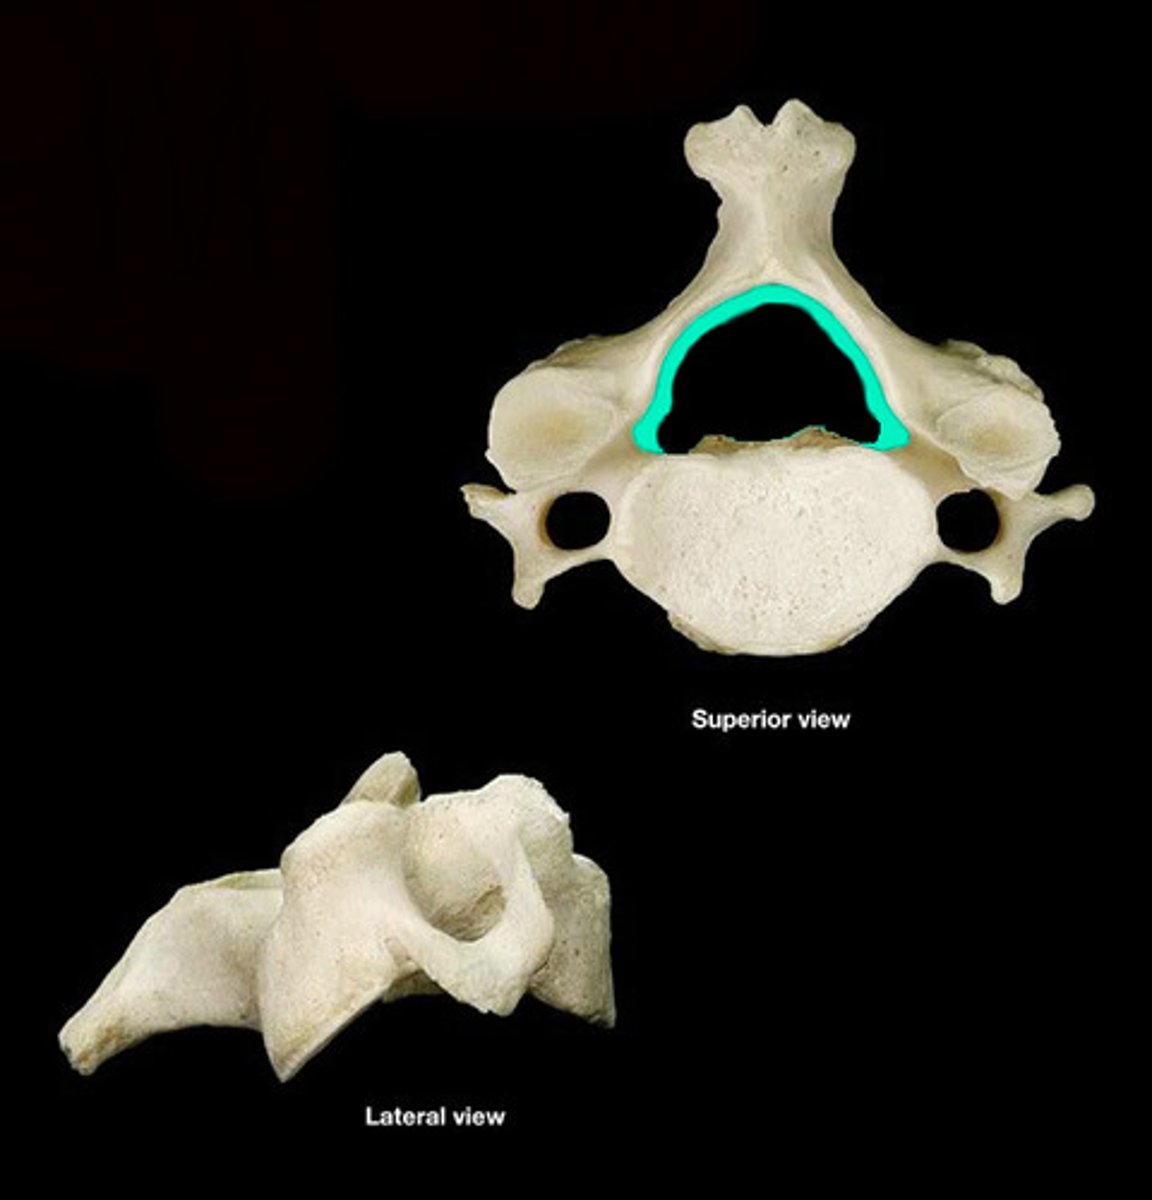

Atlas

Transverse Foramen